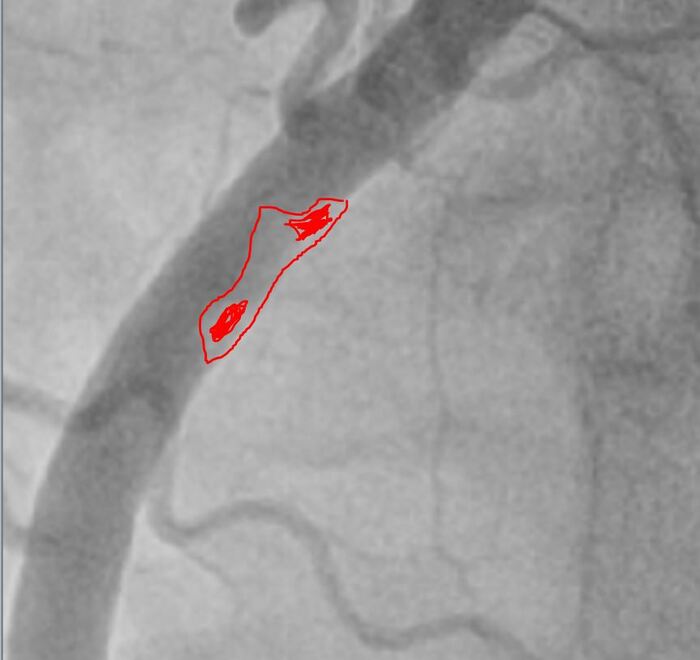

Более крупно место где все началось:

Красным зона пристеночного тромбоза, он неоднороден по плотности, рыхлый и отсюда мигрировали тромбы вниз, закупорив дистальные ветви -> как итог инфаркт.